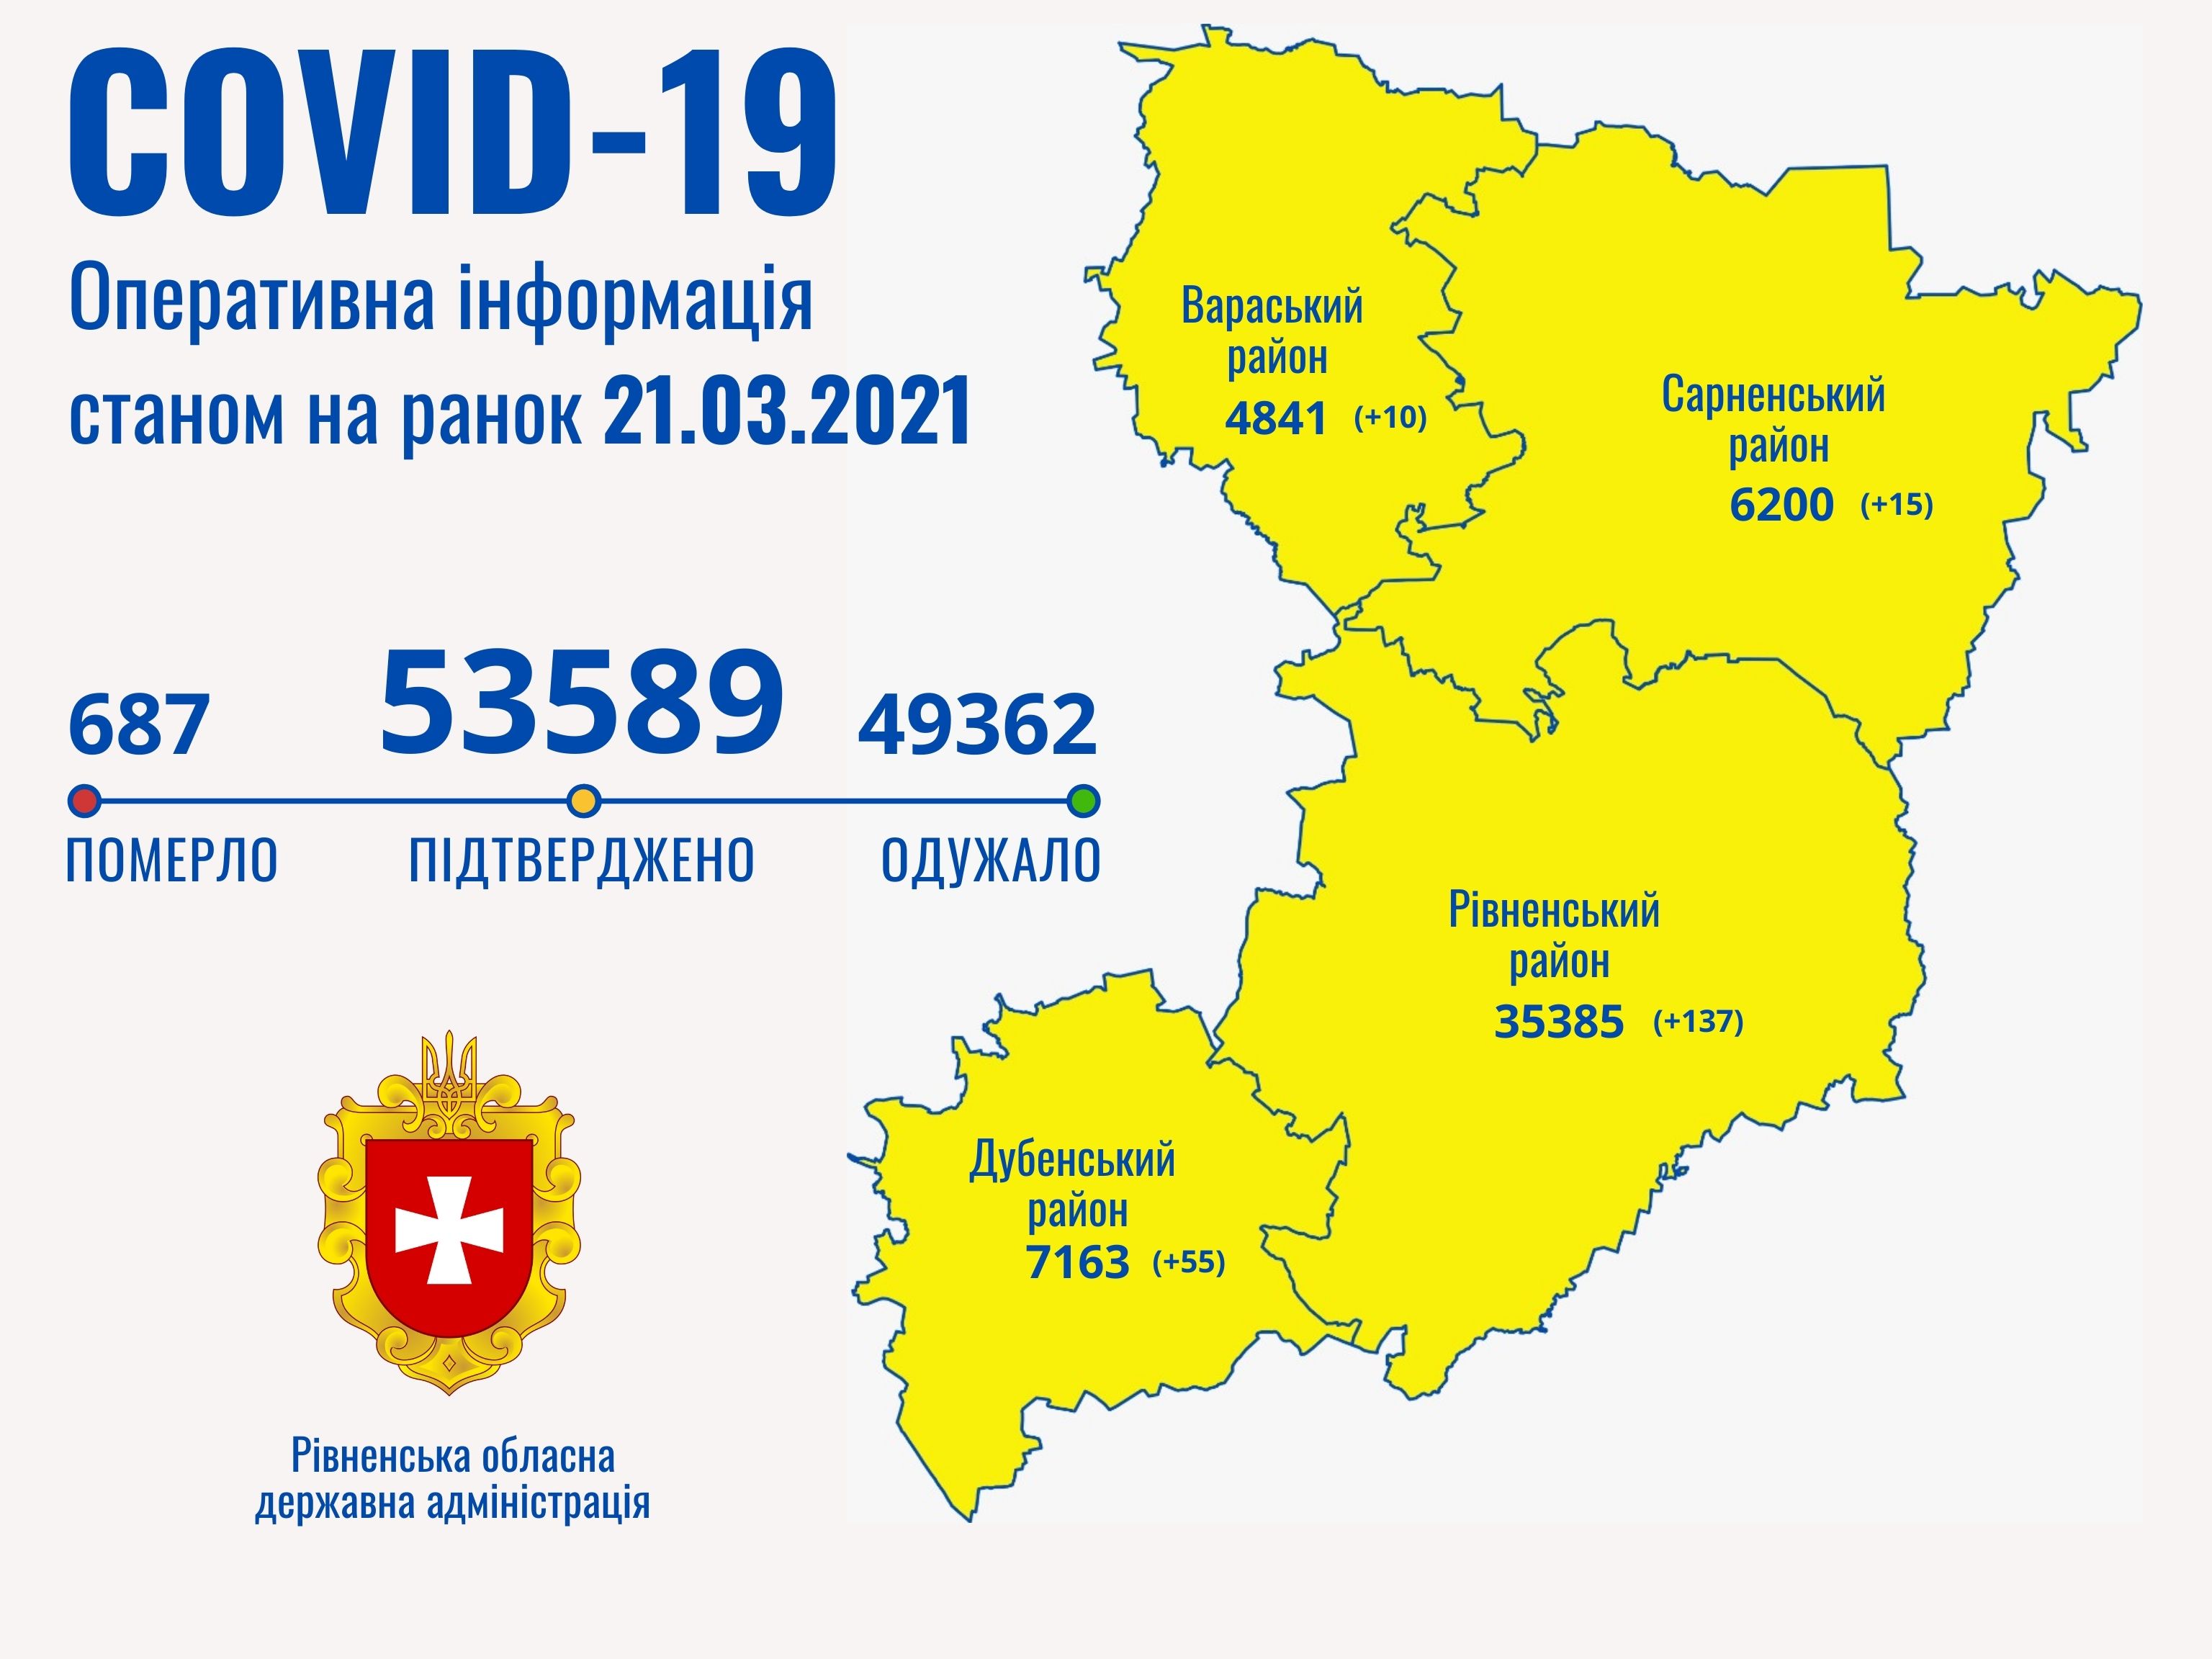

Коронавірус повертається: як стрімко зростає кількість хворих на Рівненщині (ВІДЕО)

Пів тисячі - у важкому стані, 9 жителів Рівненщини померли за добу від коронавірусу